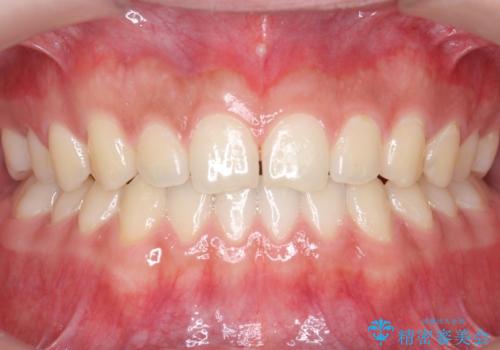

前歯のすきま 受け口 インビザラインで

- 前歯のすき間を気にして来院。

受け口もあり、前歯が端同士であたる、切端咬合となっていました。

下の歯のすき間を閉じて上の歯の内側に入るように位置付けました。

すき間もきれいに閉じ、満足していただきました。

上の前歯は下の歯と直接へりが当たっていた状態(切端咬合)だったため、形がいびつだったのは、わずかにやすりがけをして整えました。